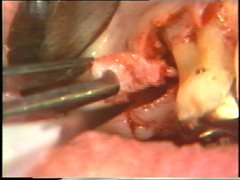

En las regiones dónde la morfología ósea impide un cierre adecuado del colgajo, se realizan recortes menores de la configuración del hueso. En este caso particular el hueso de la superficie bucal del segundo premolar impide una adaptación del colgajo. El hueso es remodelado con un cincel, con golpes cortos y suaves. Este instrumento es preferible al uso del instrumental rotatorio, porque son más difíciles de controlar y la visión del profesional se entorpece por el uso necesario del refrigerante acuoso. |